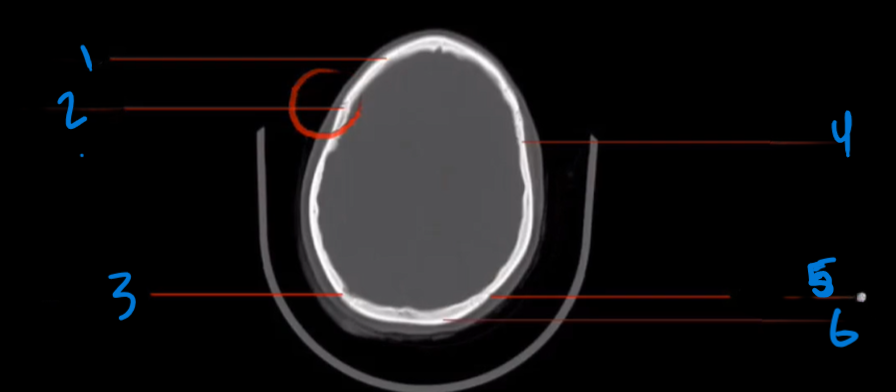

What is sagittal suture and where is it located?

●The sagittal suture runs from the frontal to the occipital bone.

Divides the parietal bones into right and left halves

Characteristic zigzag appearance is typical for cranial sutures

What is the top landmark called?

Sagittal Suture

What is the bottom landmark called?

Parietal Bone

What is this view of the skull?

Top view

What is the common view of the skull?

From inferior to superior

What does the coronal suture separates?

Frontal bone from the parietal bones, located anteriorly in the cranium

Landmark 1?

Frontal Bone

Landmark 2?

Coronal Suture

Landmark 3?

Lambdoidal Suture

Landmark 4?

Landmark 5?

Landmark 6?

Occipital Bone

Where does the occipital bone located?

posterior to the parietal bones

What is the occipital bone separated?

form parietal bones by the lambdoidal suture

What is the key structure of the occipital bone?

posterior cranium